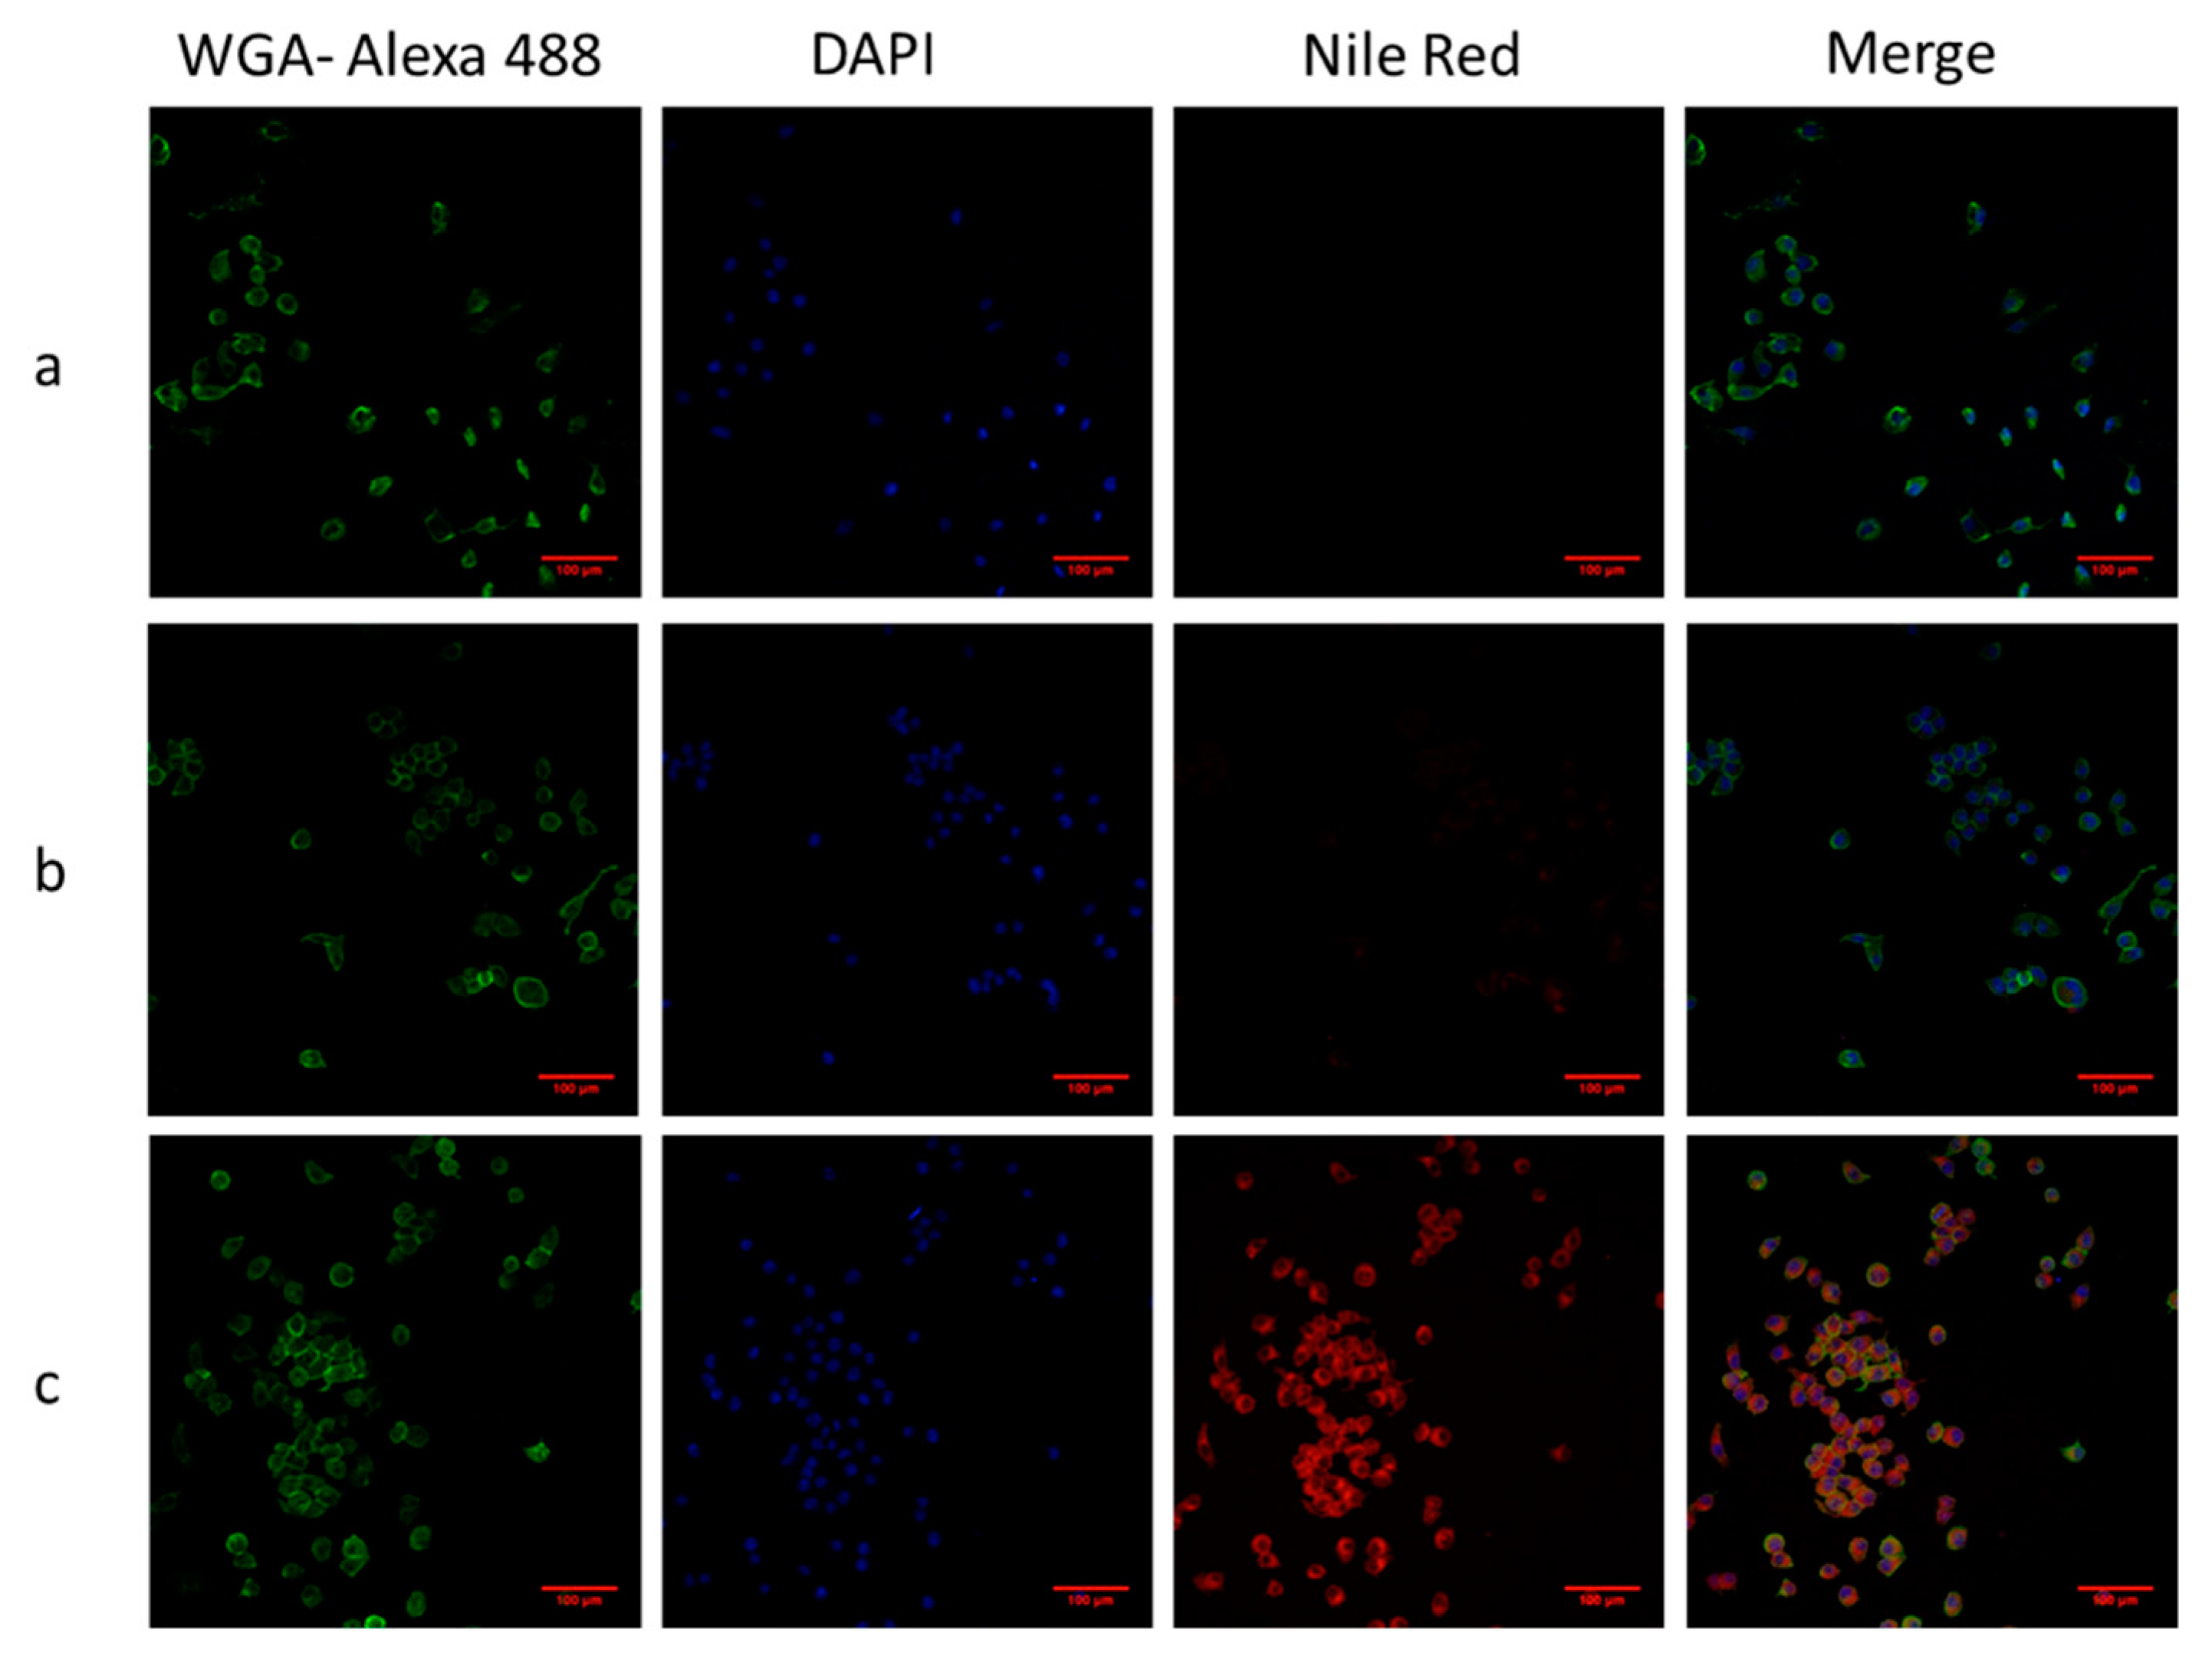

3.4.1. Prussian Blue Staining and Confocal Laser Scanning (CLSM)

3.4.2. Iron Concentration Measurement and Flow Cytometry Assays (FACs)